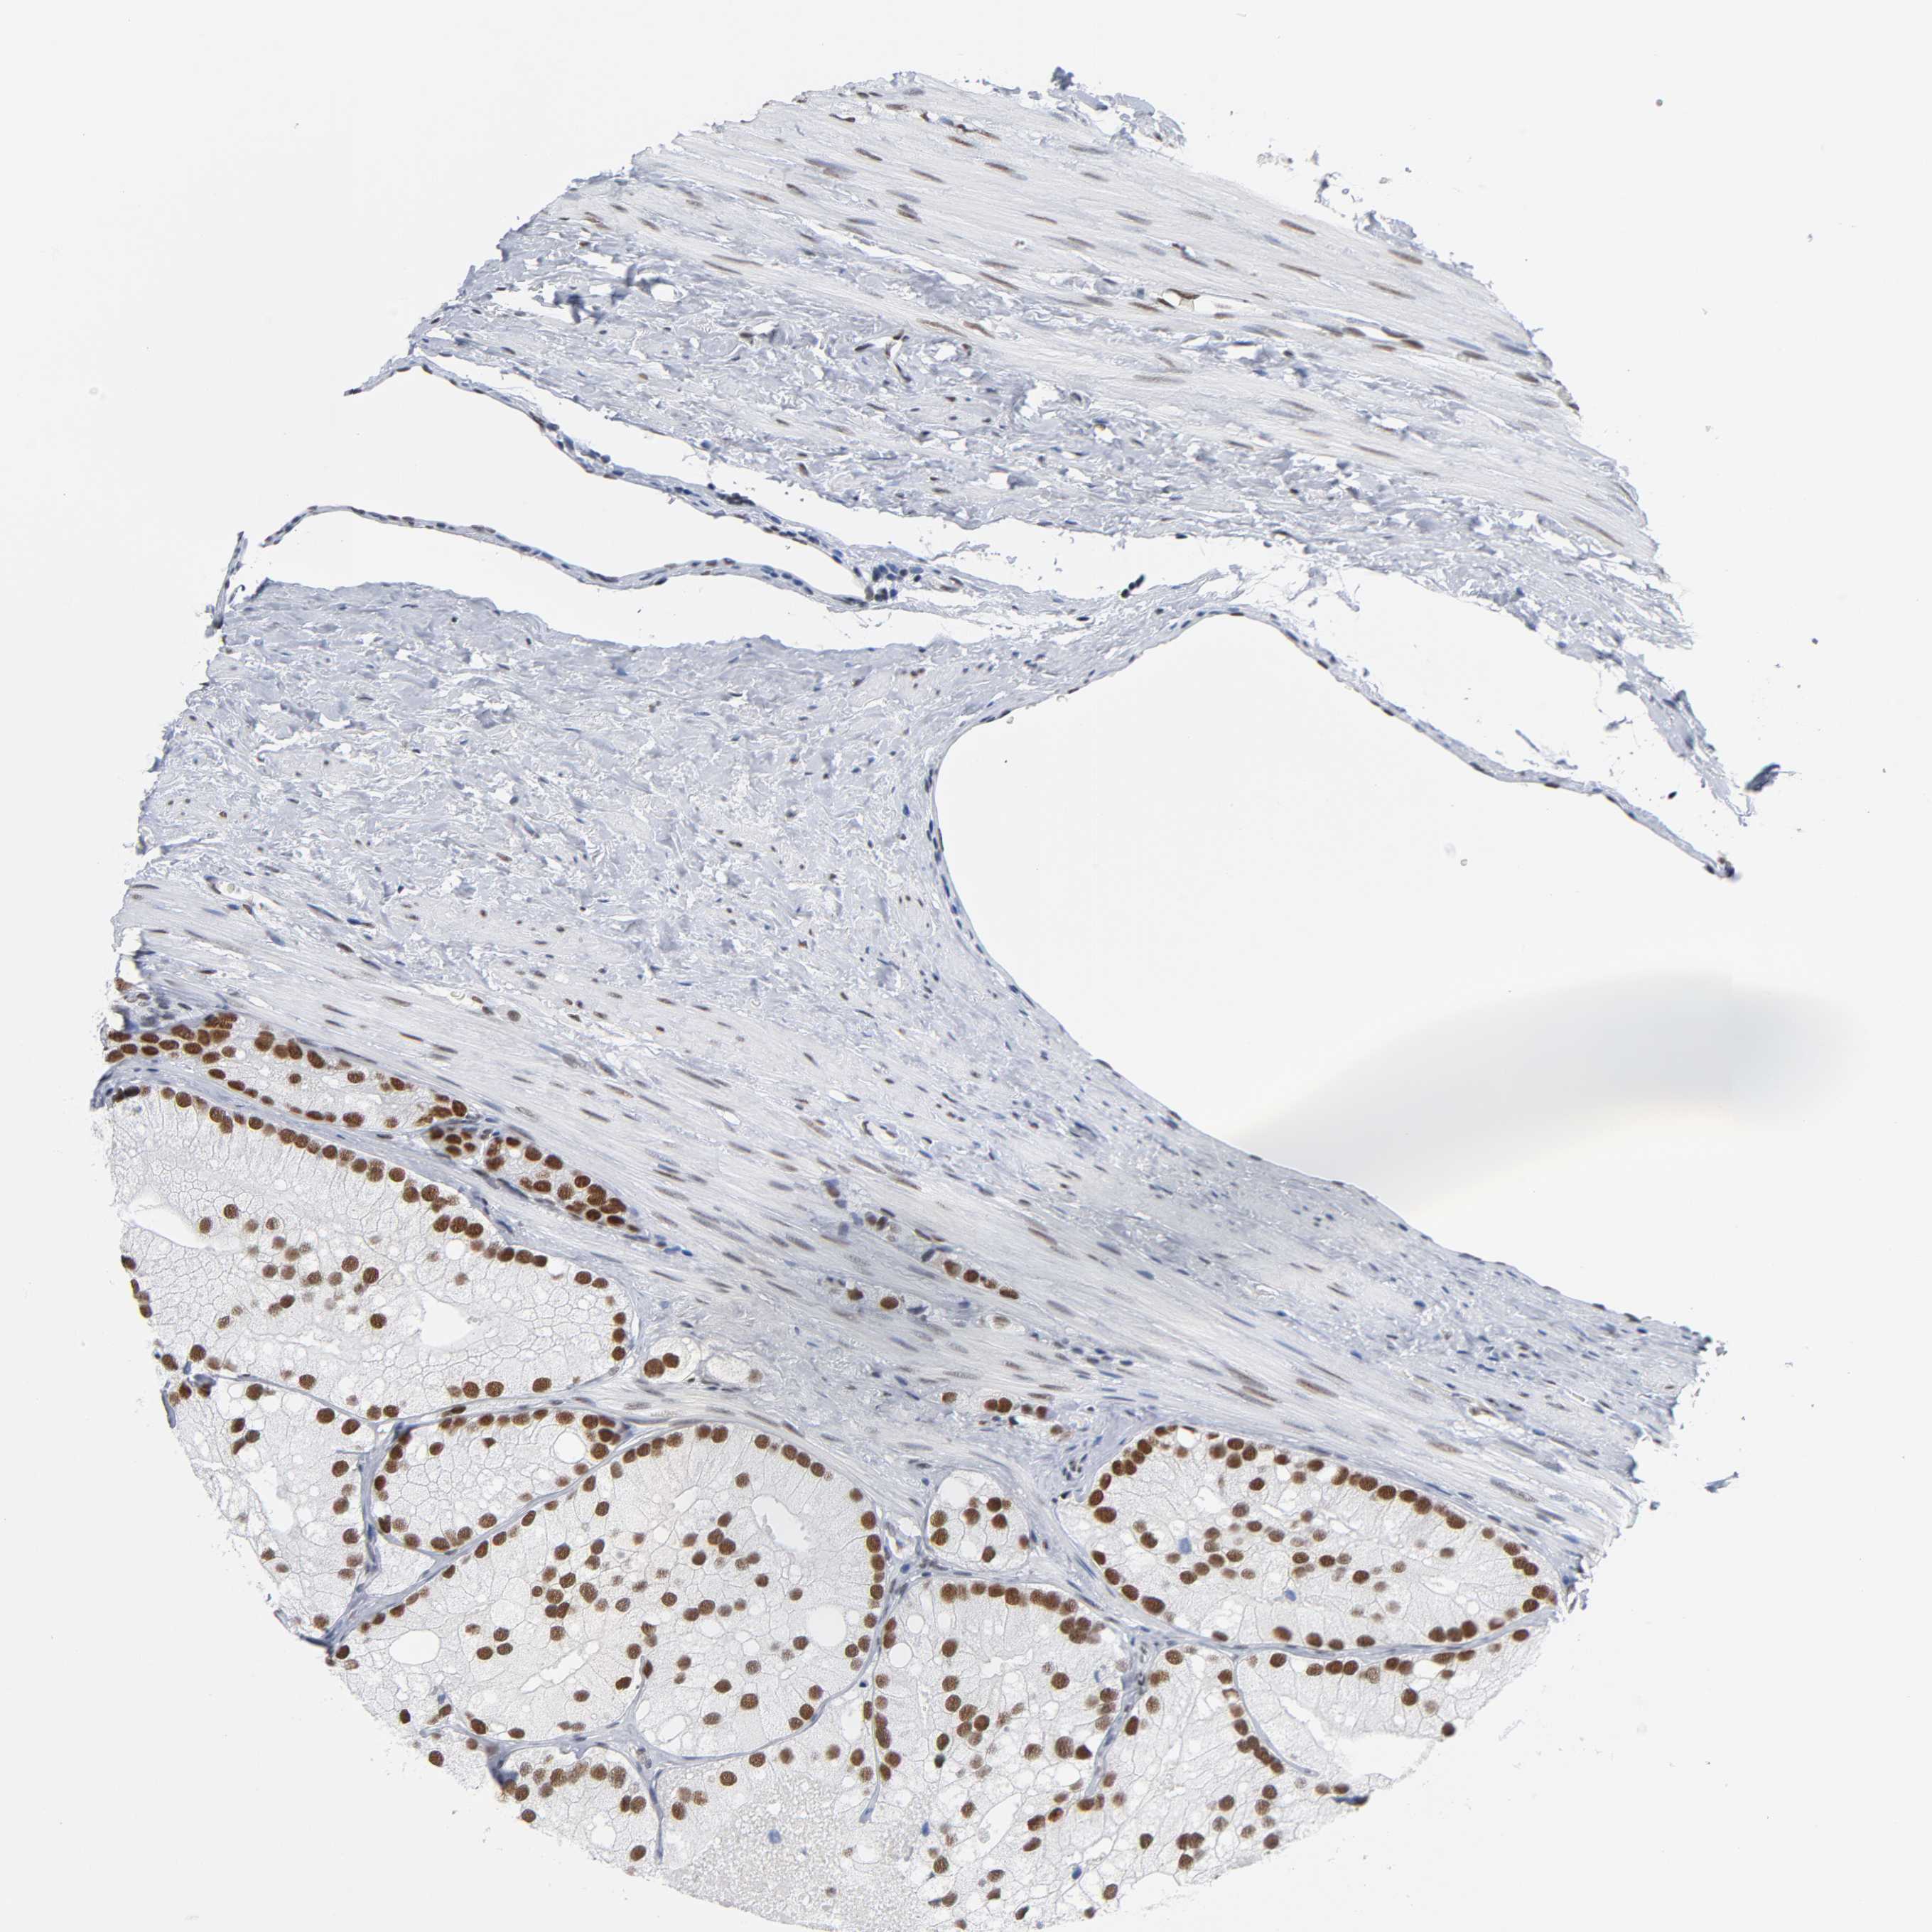

PROSTATE CANCER - Protein expressioni

A mouse-over function shows sample information and annotation data. Click on an image to view it in a full screen mode. Samples can be filtered based on level of antibody staining by selecting one or several of the following categories: high, medium, low and not detected. The assay and annotation is described here.

Note that samples used for immunohistochemistry by the Human Protein Atlas do not correspond to samples in the TCGA dataset.

Antibody stainingi

Antibody staining in the annotated cell types in the current human tissue is reported as not detected, low, medium, or high, based on conventional immunohistochemistry profiling in selected tissues. This score is based on the combination of the staining intensity and fraction of stained cells.

Each image is clickable and will lead to virtual microscopy that enables deeper exploration of all samples and also displays staining intensity scores, fraction scores and subcellular localization as well as patient and tissue information for each sample.

Antibody HPA000427

Antibody CAB004680

Staining

High

Medium

Low

Not detected

Intensity

Strong

Moderate

Weak

Negative

Quantity

>75%

75%-25%

<25%

None

Location

Nuclear

Cytoplasmic/membranous

Cytoplasmic/membranous,nuclear

Adenocarcinoma, Medium grade

Adenocarcinoma, Low grade

Adenocarcinoma, High grade